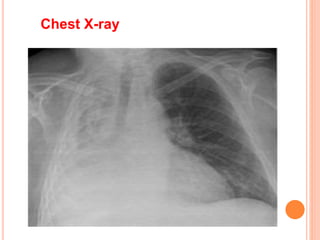

 chest x-ray: Patchy infiltrates or consolidated

areas.

Chest X-ray